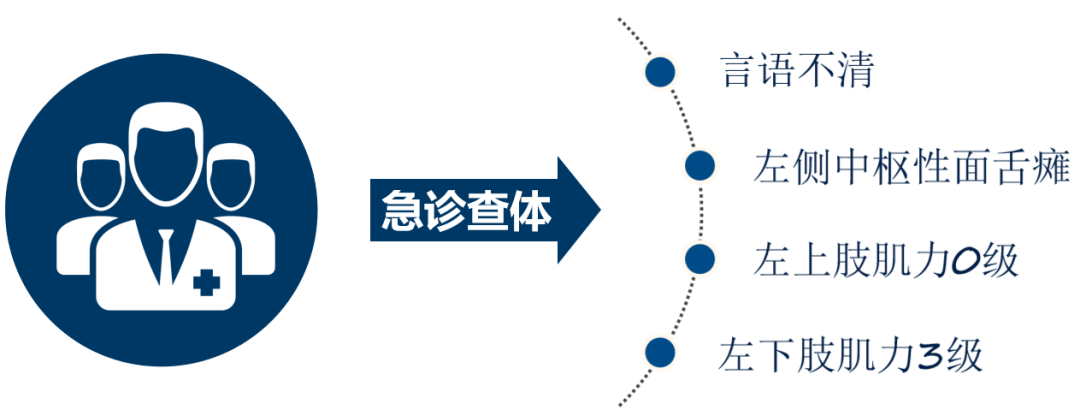

查体情况

GCS评分:15分;NIHSS评分:11分。